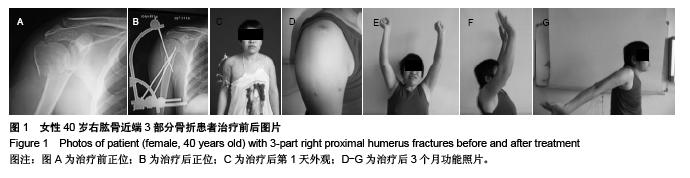

Novel closed intersection nailing external fixation repairs proximal humerus fractures: 6-month follow-up

Huang Hai-jing, He Jin-quan, Wang Jie, Jin Hong-bin. Novel closed intersection nailing external fixation repairs proximal humerus fractures: 6-month follow-up[J]. Chinese Journal of Tissue Engineering Research, 2015, 19(48): 7795-7800.